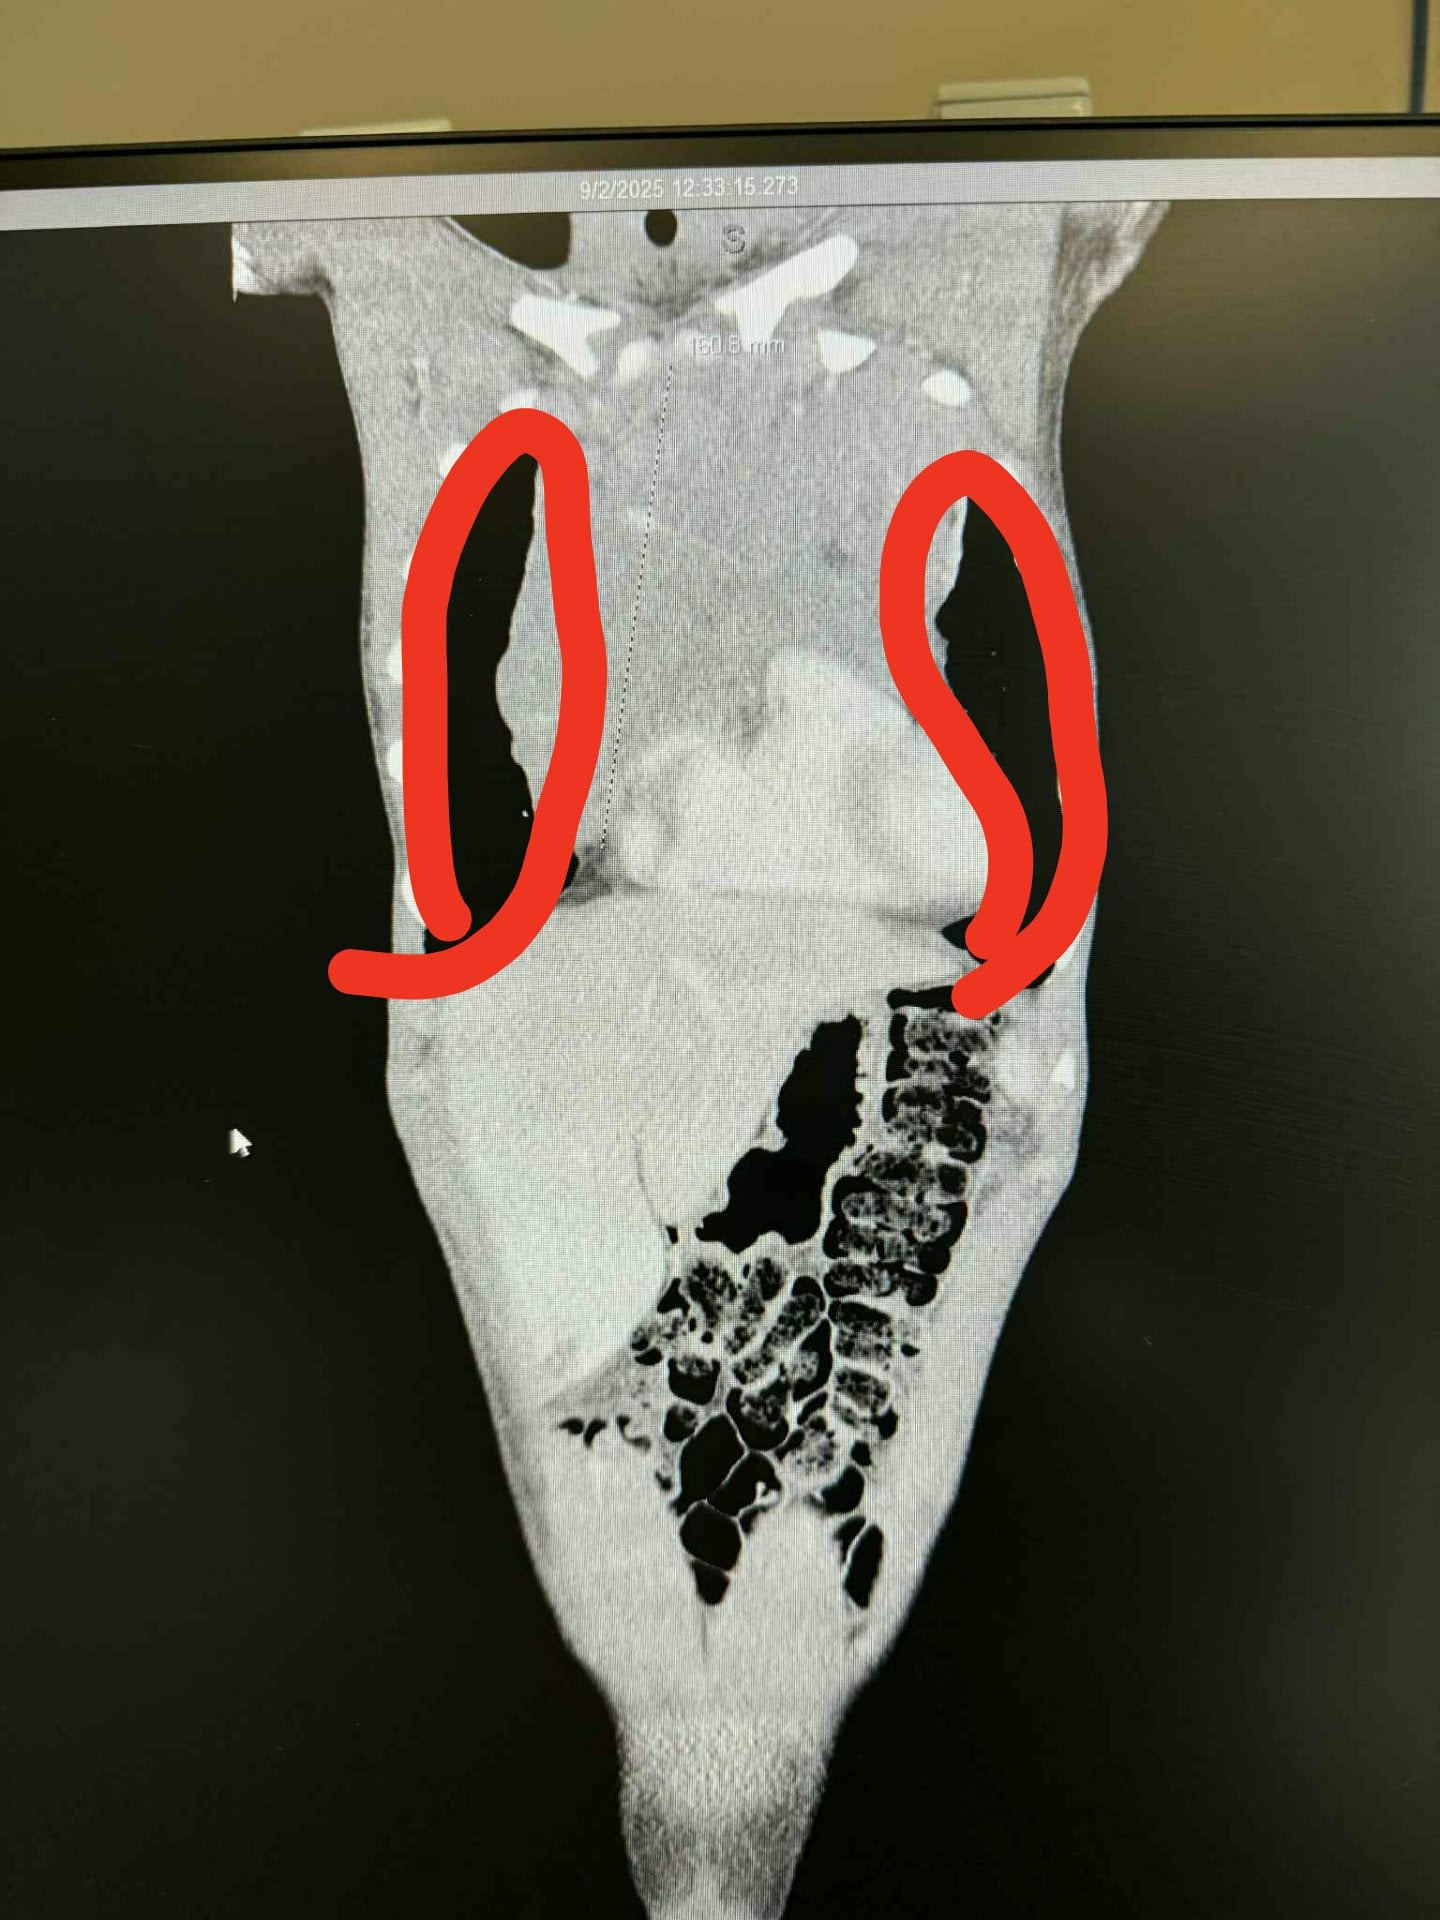

On September 2nd, 2025 Kage was brought to the Emergency Room at Whitman County Hospital complaining of a swollen throat and tongue. When doing a CT Scan on his throat they noticed the top of a large mass in his chest which prompted a second CT Scan of the abdomen. This scan found an extremely large mass pushing on his heart and lungs. He was rushed to Sacred Heart Children's Hospital in Spokane to their oncology center to have further scans and biopsies performed which confirmed Hodgkin's Lymphoma at what was though to be at Stage 2. After spending 7 days in the oncology center and a bout of chemotherapy he was sent home with us. A PET Scan done after the first round of treatment revealed additional tumors in the nodes of his lungs which upgraded the diagnosis to Stage 4.